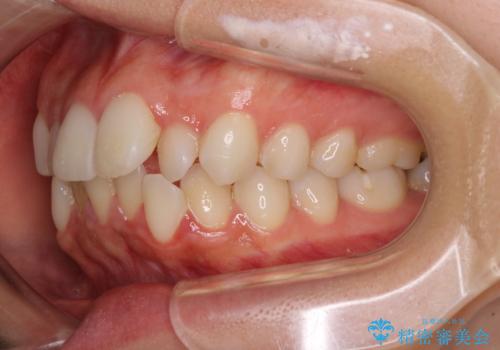

【モニター】前歯のクロスバイトをインビザラインで治療

- 前歯のデコボコとクロスバイトを気にして来院された患者様です。

上顎側切歯(上の真ん中から2番目の歯)が舌側転位している場合、インビザラインでは仕上げきれないことが多く、更には無理して動かそうとすると歯髄壊死を起こすリスクが高いと言われています。

今回は、ワイヤー装置を併用することなく、インビザライン単体で矯正治療を行うこととしました。

インビザライン特有の、奥歯の咬み合わせの問題もなく、しっかりと歯列を改善することができました。

舌側転位している上顎側切歯(内側に引っ込んでいる真ん中から2番目の歯)は、インビザラインが最も移動を苦手とする歯であり、これ以上の改善を望まれる場合にはワイヤー矯正、あるいはワイヤー矯正の併用をお勧めいたします。